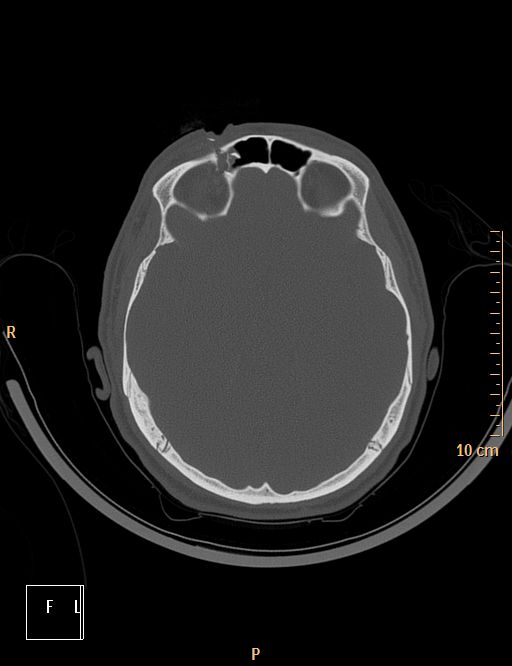

Accident de scie circulaire